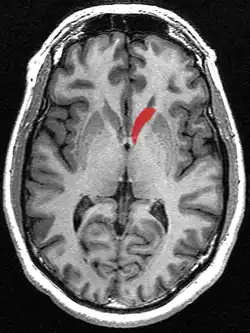

Caudate nucleus (in red) shown within the brain

This is a transverse view of the caudate nucleus from a structural MR image.

Transverse view of the caudate nucleus from a structural MR image